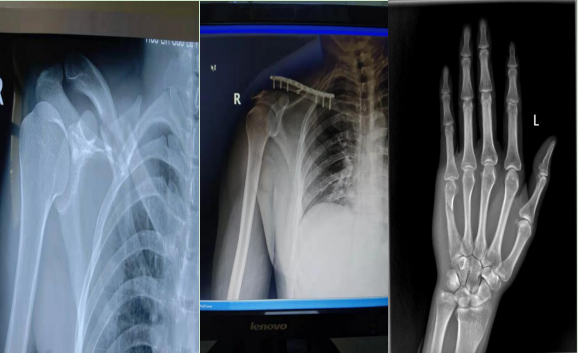

约占住院手术量的50%,项目如下:肩部及四肢骨折的钢板和(或)髓内针治疗,如:锁骨骨折、肩胛骨骨折、肱骨骨折、尺桡骨骨折、掌指骨骨折、股骨骨折、胫腓骨骨折、跖趾骨骨折切开和(或)闭合复位内固定。

关节骨科约占住院手术量的10%,项目如下:髋关节置换术(2019年新技术)肱骨外科颈骨折、尺骨鹰嘴骨折、股骨粗隆间骨折、股骨颈骨折闭合复位内固定、胫骨平台、Pilon骨折切开复位内固定术、Lisfranc损伤切开复位内固定术。老年骨性关节炎关节镜微创手术治疗等。